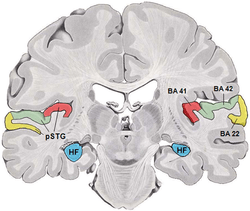

Brodmann area 41 & 42

Lateral view of human cerebrum. BA41 and 42 shown in red. | |

Brodmann area 41 is also known as the anterior transverse temporal area 41 (H). It is a subdivision of the cytoarchitectonically-defined region of cerebral cortex occupying the anterior transverse temporal gyrus (H) in the bank of the lateral sulcus on the dorsal surface of the temporal lobe. Brodmann area 41 is bounded medially by the parainsular area 52 (H) and laterally by the posterior transverse temporal area 42 (H) (Brodmann-1909).

Brodmann area 42 is also known as the posterior transverse temporal area 42 (H), and is also a subdivision of the temporal lobe. Brodmann area 42 is bounded medially by the anterior transverse temporal area 41 (H) and laterally by the superior temporal area 22 (Brodmann-1909).